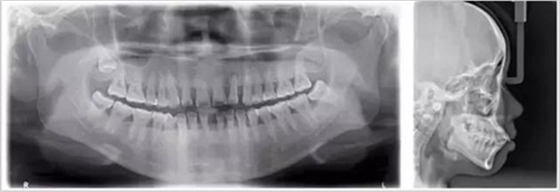

牙齒的牙根是埋在牙槽骨中的,醫(yī)生沒(méi)有透視眼,為了解患牙的牙根的形態(tài)、走向、長(zhǎng)度及根尖周有無(wú)病變及病變大小,或者懷疑有肉眼無(wú)法確認(rèn)的其它牙科問(wèn)題,都會(huì)建議患者去牙科的X光,甚至,口腔CT來(lái)全面性地確認(rèn)問(wèn)題,以訂定合適的治療計(jì)劃。

牙片對(duì)于口腔疾病的診斷尤為重要,且輻射量很小,所以只要有必要,大家不要排斥拍片診斷。